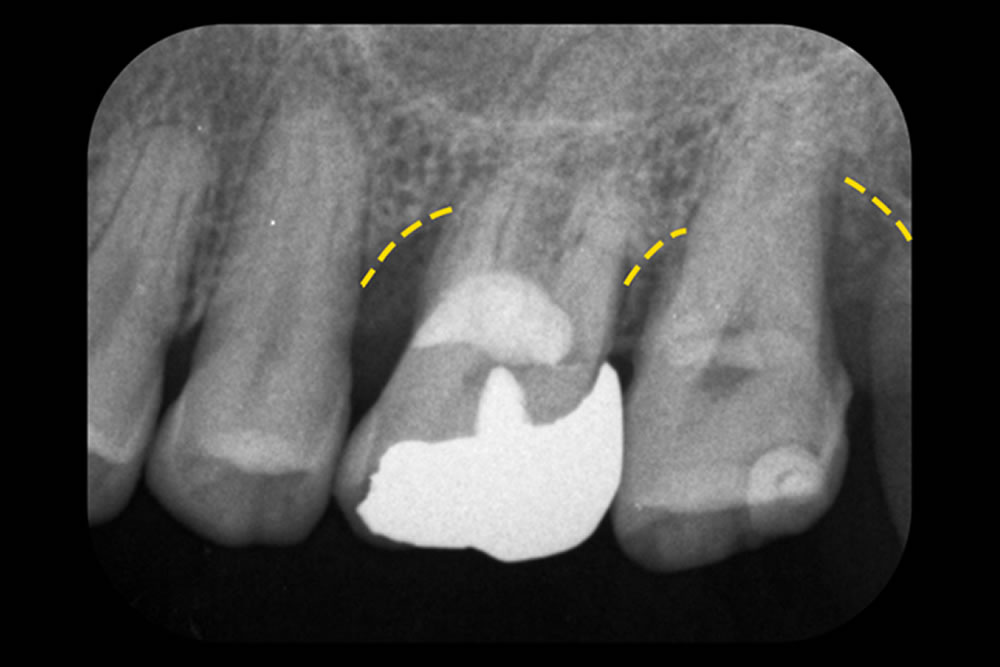

- 3.1 重症化した歯周病を手術なしで治療した症例

- 3.2 グラグラする歯を手術なしで治療した症例

- 3.3 他院で抜歯と診断された歯を手術なしで治療した症例

- 3.4 骨を部分的に欠損した歯を手術なしで改善した症例

まずは、論より証拠。日本歯周病学会専門医である当院の院長が実際に行った「重度歯周病で抜くことになる確率が高い歯を抜かなかった歯周病改善例」をご紹介します。

初診時(上写真)、右下6番目の歯は今にも抜け落ちそうな状態でしたが、重度歯周病治療【MINST】によって、症状を改善し、術後1年後(下写真)には歯周組織もしっかりと再生しました。

※外科処置なし・再生材料も使用しておりません。